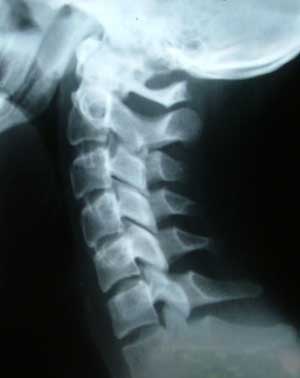

Sports-related spine injuries have continued to be a major issue in athletics. In 2010, Eric LeGrand, a football player at Rutgers University, was paralyzed while making a tackle. Three years earlier, Kevin Everett, a football player for the Buffalo Bills, injured his spine in a similar situation.

Her scholarly interests include spine trauma care, heat illness prevention and care, and injury prevention.